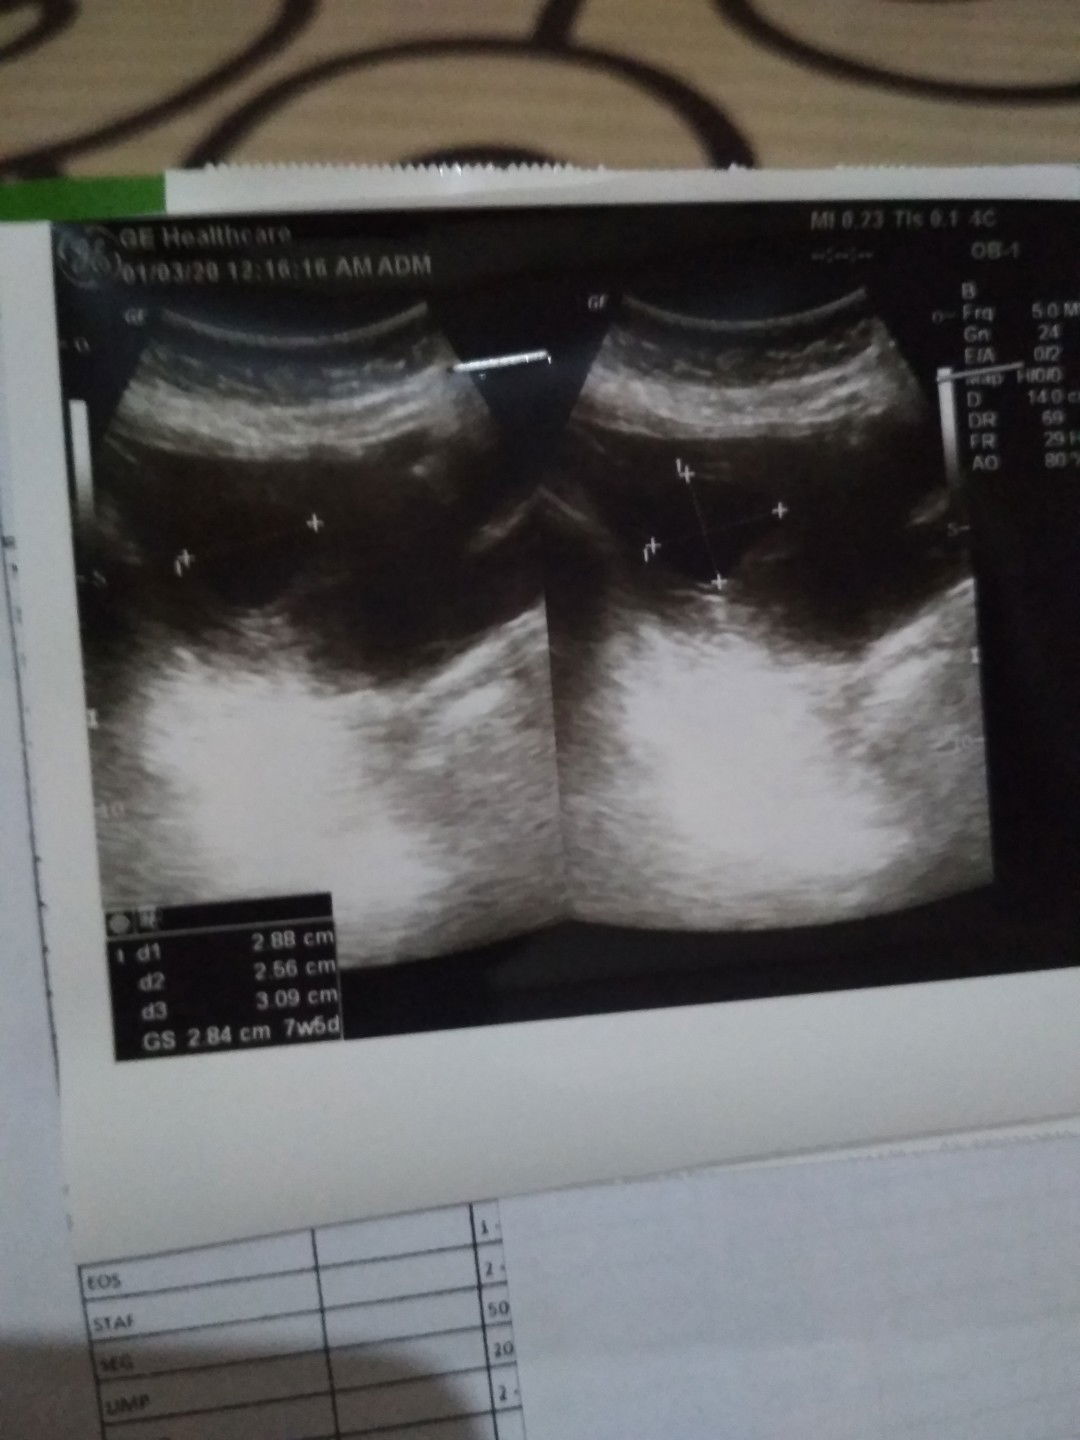

Ada kah bunda2 yg pernah hamil 10 w..tp janinnya blm keliatan detak jantungnya..kemarin saya divonis bo..setelah 2 minggu suruh balik lg..br keliatan dr usg dr vagina br keliatan janinnya..tp detak jantungnya blm keliatan..

Bun..ada kah disini..sudah dicek kata dokter janin tidak berkembang..alias kosong..trs dikasih obat penguat kandungan..setelah seminggu hasilnya ada janinnya ato tetap masih kosong janinnya..tolong bun..saya galau sekali..takut nanti seminggu lagi disuruh balik kedokter..hasilnya tetep ngga ada janinnya alias kosong..saya takut ngebayangin harus kuret..skrng usia kandungan saya mau masuk 8 minggu..

Bun..ada kah bunda2 yg sama dgn saya..usg bln lalu positif hamil bagus aja kata dokter..sekarang balik lg ternyata blm keliatan janinnya..katanya tidak berkembang janinnya..katanya hasilnya 50- 50 % ..skrng dikasih obat penguat kandungan..minggu depan disuruh balik lg..untuk liat janinnya berkembang ato tidak..tolong masukannya bunda2..biar saya tidak galau sendiri..ini kehamilan saya yg ke3..